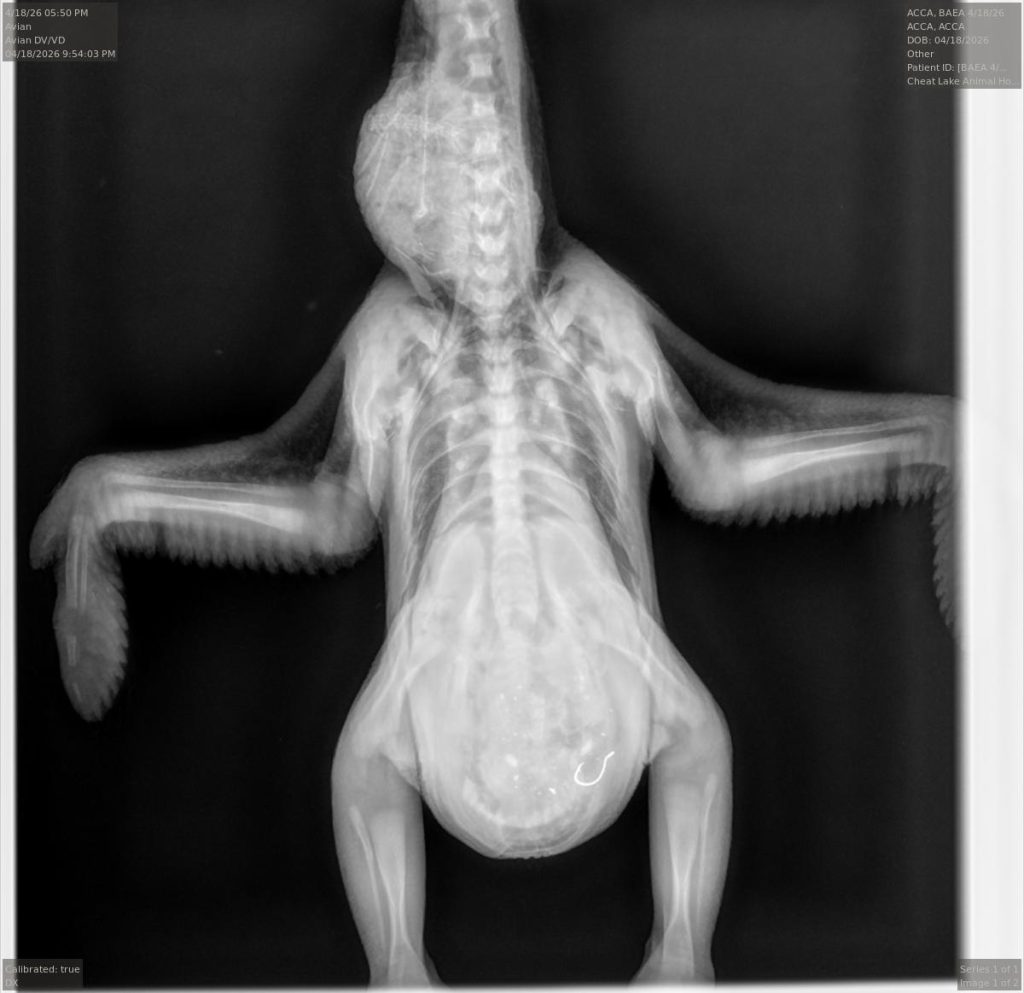

Dr. Jesse Fallon, director of veterinary medicine for the center and a veterinarian at Cheat Lake Animal Hospital where the center is based, took over the story from there. “We decided that the best chance for the eagle to have a positive outcome was to capture it and get that fishhook out of there,” he said.

Fallon and his team examined it when it arrived. The bird was quiet and responsive, had the fishing line hanging out of its mouth, but was otherwise in reasonable health for a 2-week-old eagle chick.

They first tried using endoscopy – a camera on a scope – but there was too much food in the bird’s stomach to be able to see the hook.

So they turned to surgery. His veterinary technician Cayce Dakon handled the anesthesia while Tricia Mayle was his surgical assistant.

He made an abdominal incision and removed the hook, which was still attached to the synthetic worm lure and the fishing line. USS11 was out of surgery around 8 p.m., he said.